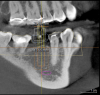

Fig. 10 through Fig. 15 By knowing about the buccal concavity in advance, the implant could be moved mesially and placed through a tissue punch using a guide. This saved the patient the discomfort and expense of a flap and possible graft.

Figure 10

Figure 11

Figure 12

Figure 13

Figure 14

Figure 15